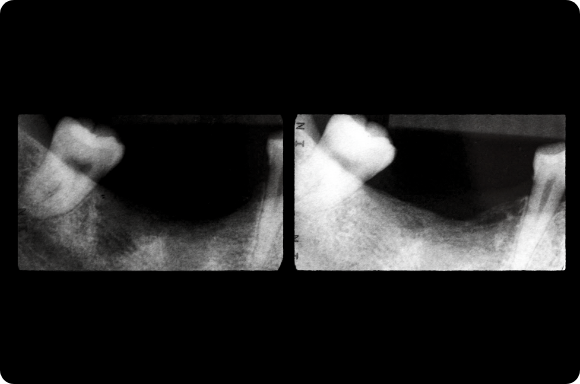

Ce cours de niveau maîtrise aborde à la fois la prévention et la gestion des complications chirurgicales et restauratrices. Dans le domaine chirurgical, la présentation se concentre sur l’échec précoce de l’implant et la maladie péri-implantaire ultérieure. Les concepts prothétiques comprendront la conception de prothèses préventives, le retrait des vis/piliers et un séquençage qui reconnaît l’importance de l’expérience du patient.

Le programme consacré à l’implantologie est une série de cours interactifs basés sur les procédures qui utilisent des cas individuels pour enseigner le traitement actuel des implants. Cette approche est contraire à l’éducation dentaire conventionnelle qui se concentre davantage sur les sujets et la théorie didactiques. L’objectif de cette approche pédagogique est de mettre en évidence les patients et les procédures rencontrés dans la pratique clinique quotidienne, où les concepts les plus importants sont observés et discutés dans de multiples scénarios cliniques.

Sur la base des procédures : Cours de niveau 6

Maîtrise : Cours de niveau 8